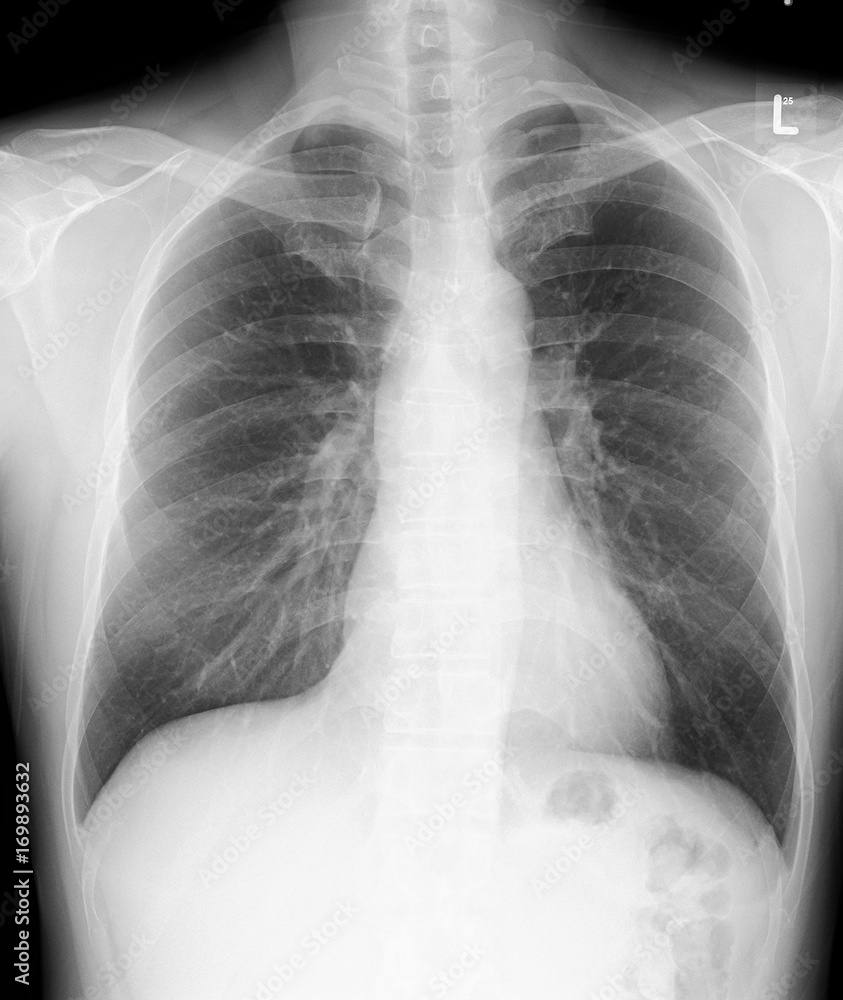

Film regular chest PA. Heart size, diaphragm and costophrenic sulci are

Film regular chest PA. Heart size, diaphragm and costophrenic sulci are Meaning Of Unremarkable Chest X Ray Use this article to gain a basic understanding of chest x. “normal” means that the result is exactly what the radiologist. if the radiologist does not see anything concerning it may say “normal” or “unremarkable.” below is an example of a report style often used for a ct scan. In fact every radiologst should be an expert in chest. Meaning Of Unremarkable Chest X Ray.